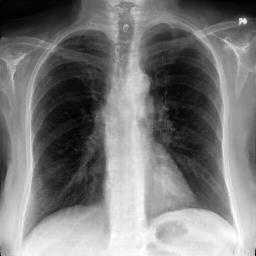

Fig. 3: Anonymization results. Real images XRX_{R} randomly selected from the training, validation, and test sets are displayed in the first column. The corresponding reconstructed images X^R\hat{X}_{R} are displayed in the second column. The anonymized images XAX_{A} are displayed in the last three columns.

Qualitative Results The visualization results are shown in Fig. 3. In this figure, the anonymized images optimized using only the utility loss ut\mathcal{L}_{ut} (column 3) exhibit greater visual similarity to their real counterparts (column 1), while those optimized using only the identity loss id\mathcal{L}_{id} (column 4) appear more distinct from their originals. Additionally, the anonymized images optimized with both the ut\mathcal{L}_{ut} and the id\mathcal{L}_{id} (column 5) strike a balance, appearing more realistic by simultaneously considering both identity removal and utility preservation.